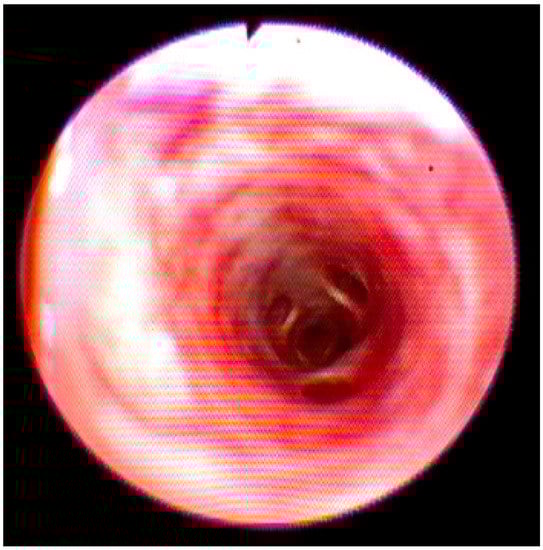

Cytological evaluation performed on the sample collected after BAL evidenced normal ciliated cells and rare macrophages (Figure 3).

Figure 3. Normal cytological findings with presence of proteinaceous material, normal cylindrical ciliated cells, absence of etiological agents.